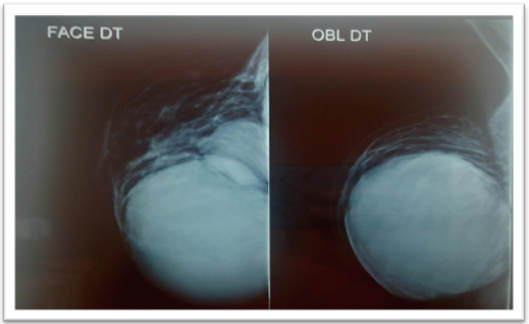

Mammography reveals two voluminous masses distorting the mammary contours and occupying almost all the right internal quadrants. The larger mass is located on the upper inner quadrant of the right breast, while the second is located in the lower inner quadrant of the right breast, they are high in tone, well-defined, with regular contours (figure 2).

Figure 2. Mammographic Appearance